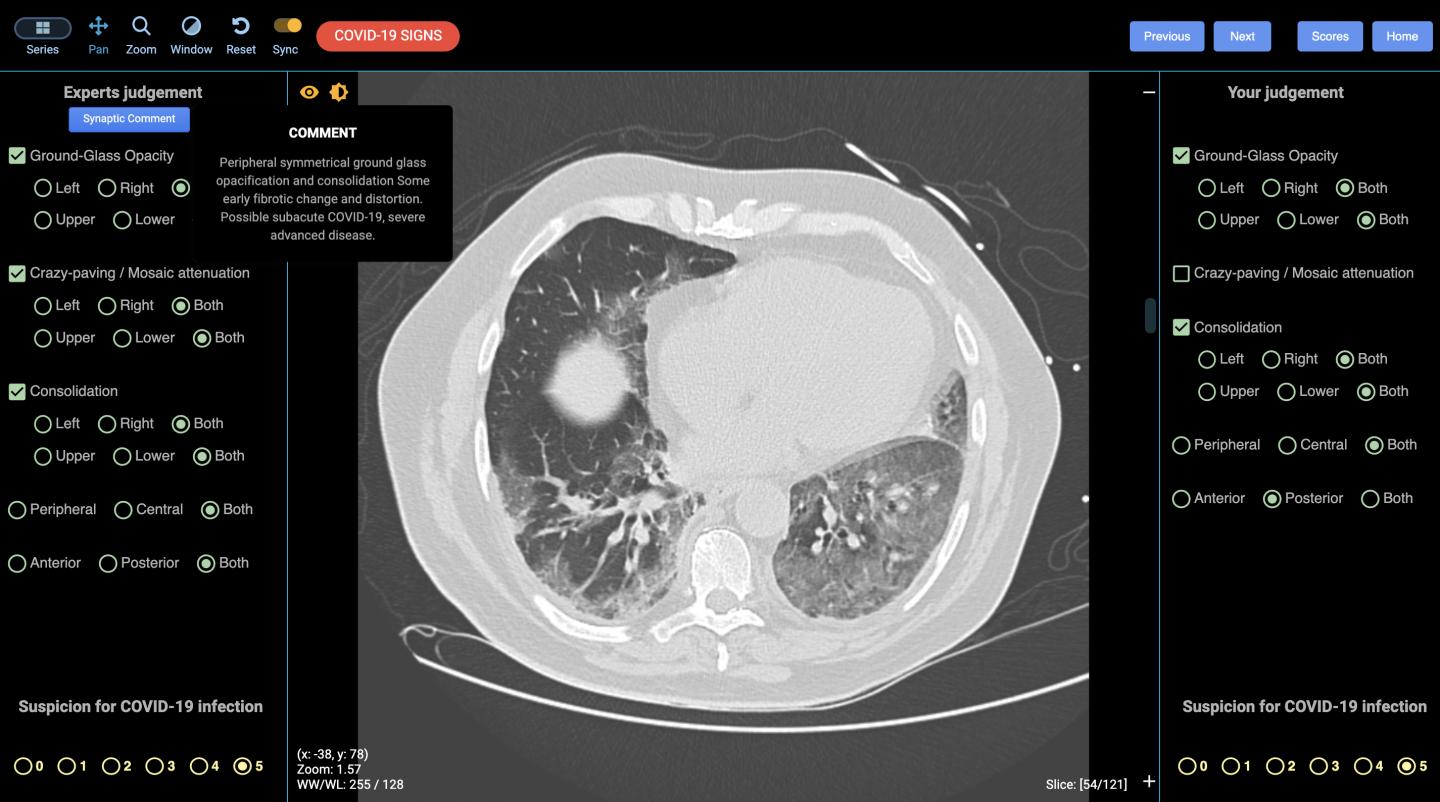

The cloud-based life-saving technology, developed by Australian-based radiation and imaging experts DetectED-X, will help doctors and radiologists diagnose cases faster and more accurately. Computed tomography (CT) lung scans, which produce cross-sectional images using X-rays and computers, have typically been used after swabs are taken, to identify the extent and location of the disease; the CT scans produce images within minutes and are also able to diagnose COVID-19 in the very early stages that escape detection with the nucleic acid tests.

DetectED-X's approach, which includes algorithms to improve radiologist skills and identifying where errors were made on images in the online training sessions, has been shown to improve results significantly*. The CovED platform uses CT images from cases with appearances of COVID-19 arising from Australia (Queensland, Victoria, NSW) and collaborators in Europe.

Through CovED, individual clinicians can assess their performance on images on screen, and receive immediate feedback including performance scores used in the industry. The image files personalised for each clinician are instantly returned showing any errors in their virtual diagnosis and the difficulty level is increased over time.

Radiologic detection is the front-line tool for identifying early lung changes such as acute presentations such as bilateral ground-glass opacities and consolidative pulmonary opacities (a type of pneumonia) , with these progressing to consolidation, greater total lung involvement, linear opacities, crazy-paving patterns and the reverse halo sign at later stages . High resolution computed tomography (CT) which outperforms plain chest X-rays , is sensitive and specific for COVID-19 infection, even at early stages of concentrated viruses in a sample, when viral titres are equivocal. It is routine, involving low radiation dose and can be acquired rapidly.

While CT can display the signs, the subtle lung appearances representing early stage disease remain challenging for non-specialized reporters resulting in significant diagnostic errors: the sensitivity of CT for detection of lung lesions can be as low as 70 percent for experienced and 51 percent for less experienced radiologists . For HRCT to play a useful role in facilitating early COVID-19 diagnosis at the scale necessary, rapid improvements in reporting accuracy are needed.